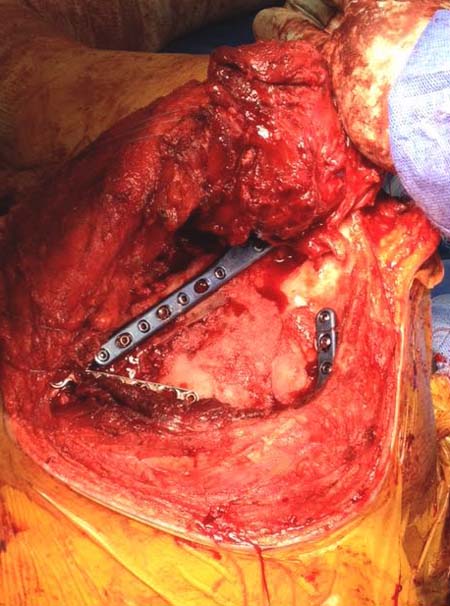

Здесь пример, стандартные снимки: плечо и лопатка прямой снимок, аксиллярный и косой снимки (Y-view) и фиксация пластинами по краям, где имеется более твердая кость. Специальные пластины, хотя любая 2.7 или 3.5 мм тубулярная пластина подойдут для фиксации перелома. Риск операции - это повреждение нерва во время доступа и ре-фиксация ротаторной манжетки если потребуется широкий доступ!